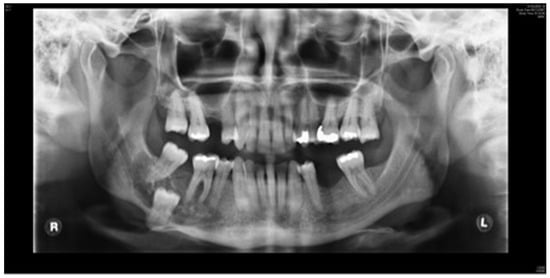

Figure 1.

Clinical case. Orthopantomography (OPT) showing calcifying epithelial odontogenic tumor affecting the right mandible.